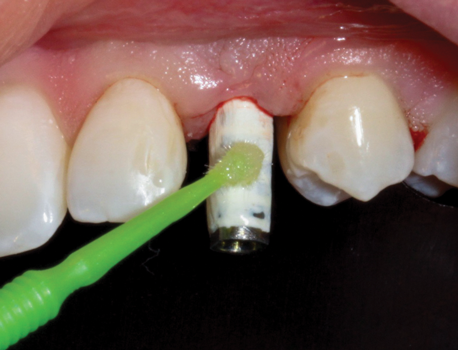

(39.) The composite tooth shell was modified to fit around the abutment, positioned intraorally, and bonded to the abutment with flowable composite in the incisal half.

Figure 39